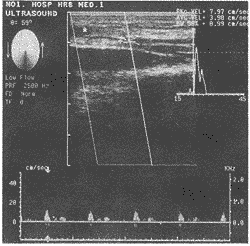

7例患者9条动脉中,7条桡动脉血流频谱呈三相波或二相波,但舒张期均呈较持续的血流频 谱。吻合口处血管内径患侧(2.54±0.31mm)与健侧对比(2.60±0.29mm)无显著差异(P > 0.01),吻合口处血流显示良好,患侧时间平均血流速度(TAV:8.13±0.50cm/s)与健侧 相比(8.45±0.52cm/s)无显著差异(P>0.01),血流量两者相比亦无显著差异(患侧2 4.12±0.26ml/m,健侧26.03±0.31ml/m),但收缩期峰值血流速度(PSV)健侧(40.15±5 .46cm/s)较患侧(26.17±3.31cm/s)明显增高(P<0.01)。余两例腕部离断伤患者, 尺动脉吻合口处内径均缩小,与其近端正常段血管内径相比狭窄程度分别为:(2.0 -1.0)/2.0=50%及(2.1-0.8)/2.1=62%,血管内径狭窄,血流显示差,血流频谱低平(图1、2)。

图1 正常尺动脉频谱

图2 患侧尺动脉频谱